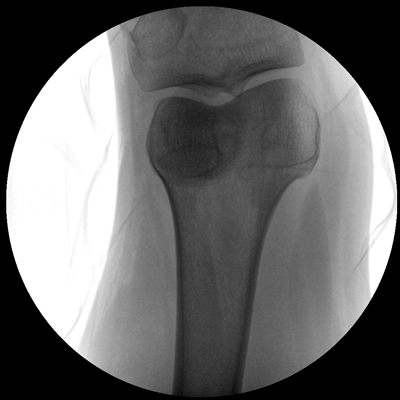

小巧輕便 超凡靈動 PLX116

●一體化機(jī)架設(shè)計,占地空間小,移動靈活

●一人獨立操作,即可完成C形臂的移動與曝光

●全數(shù)字化百萬像素影像系統(tǒng),圖像清晰

●多種工作模式任意選擇,滿足多種臨床需求